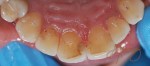

When passion becomes your profession..making people smile becomes your habit! here’s my recent case of cosmetic dentistry: